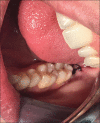

Aim: The present study aimed to comparatively evaluate the clinical outcomes and periodontal status of the adjacent second molar, when two different flap designs, namely, the envelope and the modified triangular flap designs were used.

Materials and methods: Sixty female patients with bilateral impacted third molars completed the study with envelope flap on one side and modified triangular flap design on the other side of the mandible for third molar removal. Clinical parameters including pain, dehiscence and swelling were assessed postoperatively and periodontal probing depth (PPD) on the distal aspect of adjacent second molar were assessed both pre- and post-operatively.

Conclusion: The study revealed that the modified triangular flap had lesser postoperative PPDs and dehiscence. The envelope flap was better when swelling was analyzed. The pain scores, though slightly higher for the modified triangular flap group, were not statistically significant.